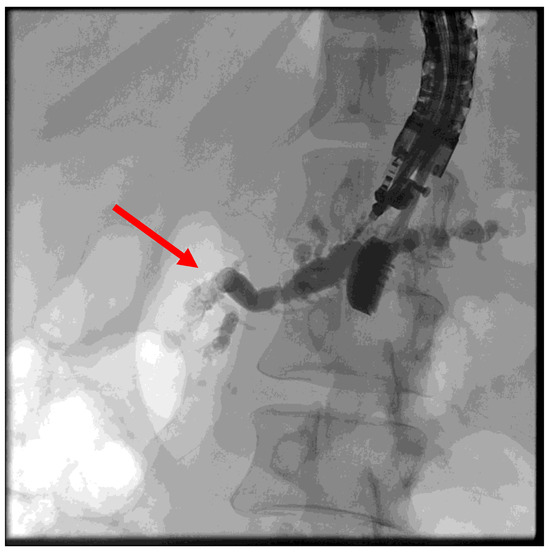

(B) EUS-guided pancreatic duct drainage (EUS-PD): If the wire cannot pass through the papilla or if the papilla is unreachable with a standard duodenoscope or enteroscope (e.g., post-gastrectomy, Roux-en-Y reconstruction, Kausch–Whipple surgery; see the above), the wire is advanced as far as possible into the pancreatic duct following an EUS puncture. An access site is then created along the wire using a Will HF ring knife (MTW Endoskopie Manufaktur W. Haag KG, Wesel, Germany) followed by dilatation of the typically transgastric access using a 6-mm bile duct dilatation balloon (Boston Scientific, Ratingen, Germany). The choice of prosthesis, which is inserted, depends on factors such as the site and width of the pancreatic duct system or the direction of the puncture. If a wide pancreatic duct is punctured near the obstruction, antegrade drainage (pancreaticogastrostomy/pancreaticoduodenectomy) can be attempted by using a self-expanding metal stent (SEM or LAMS, Boston Scientific, Ratingen, Germany) or a straight plastic Amsterdam prosthesis (Medi-Globe, Achenmühle, Germany) (Figure 5).

Figure 6. Puncture of the pancreatic duct in the tail segment with unsuccessful wire advancement due to stricture (red arrow).